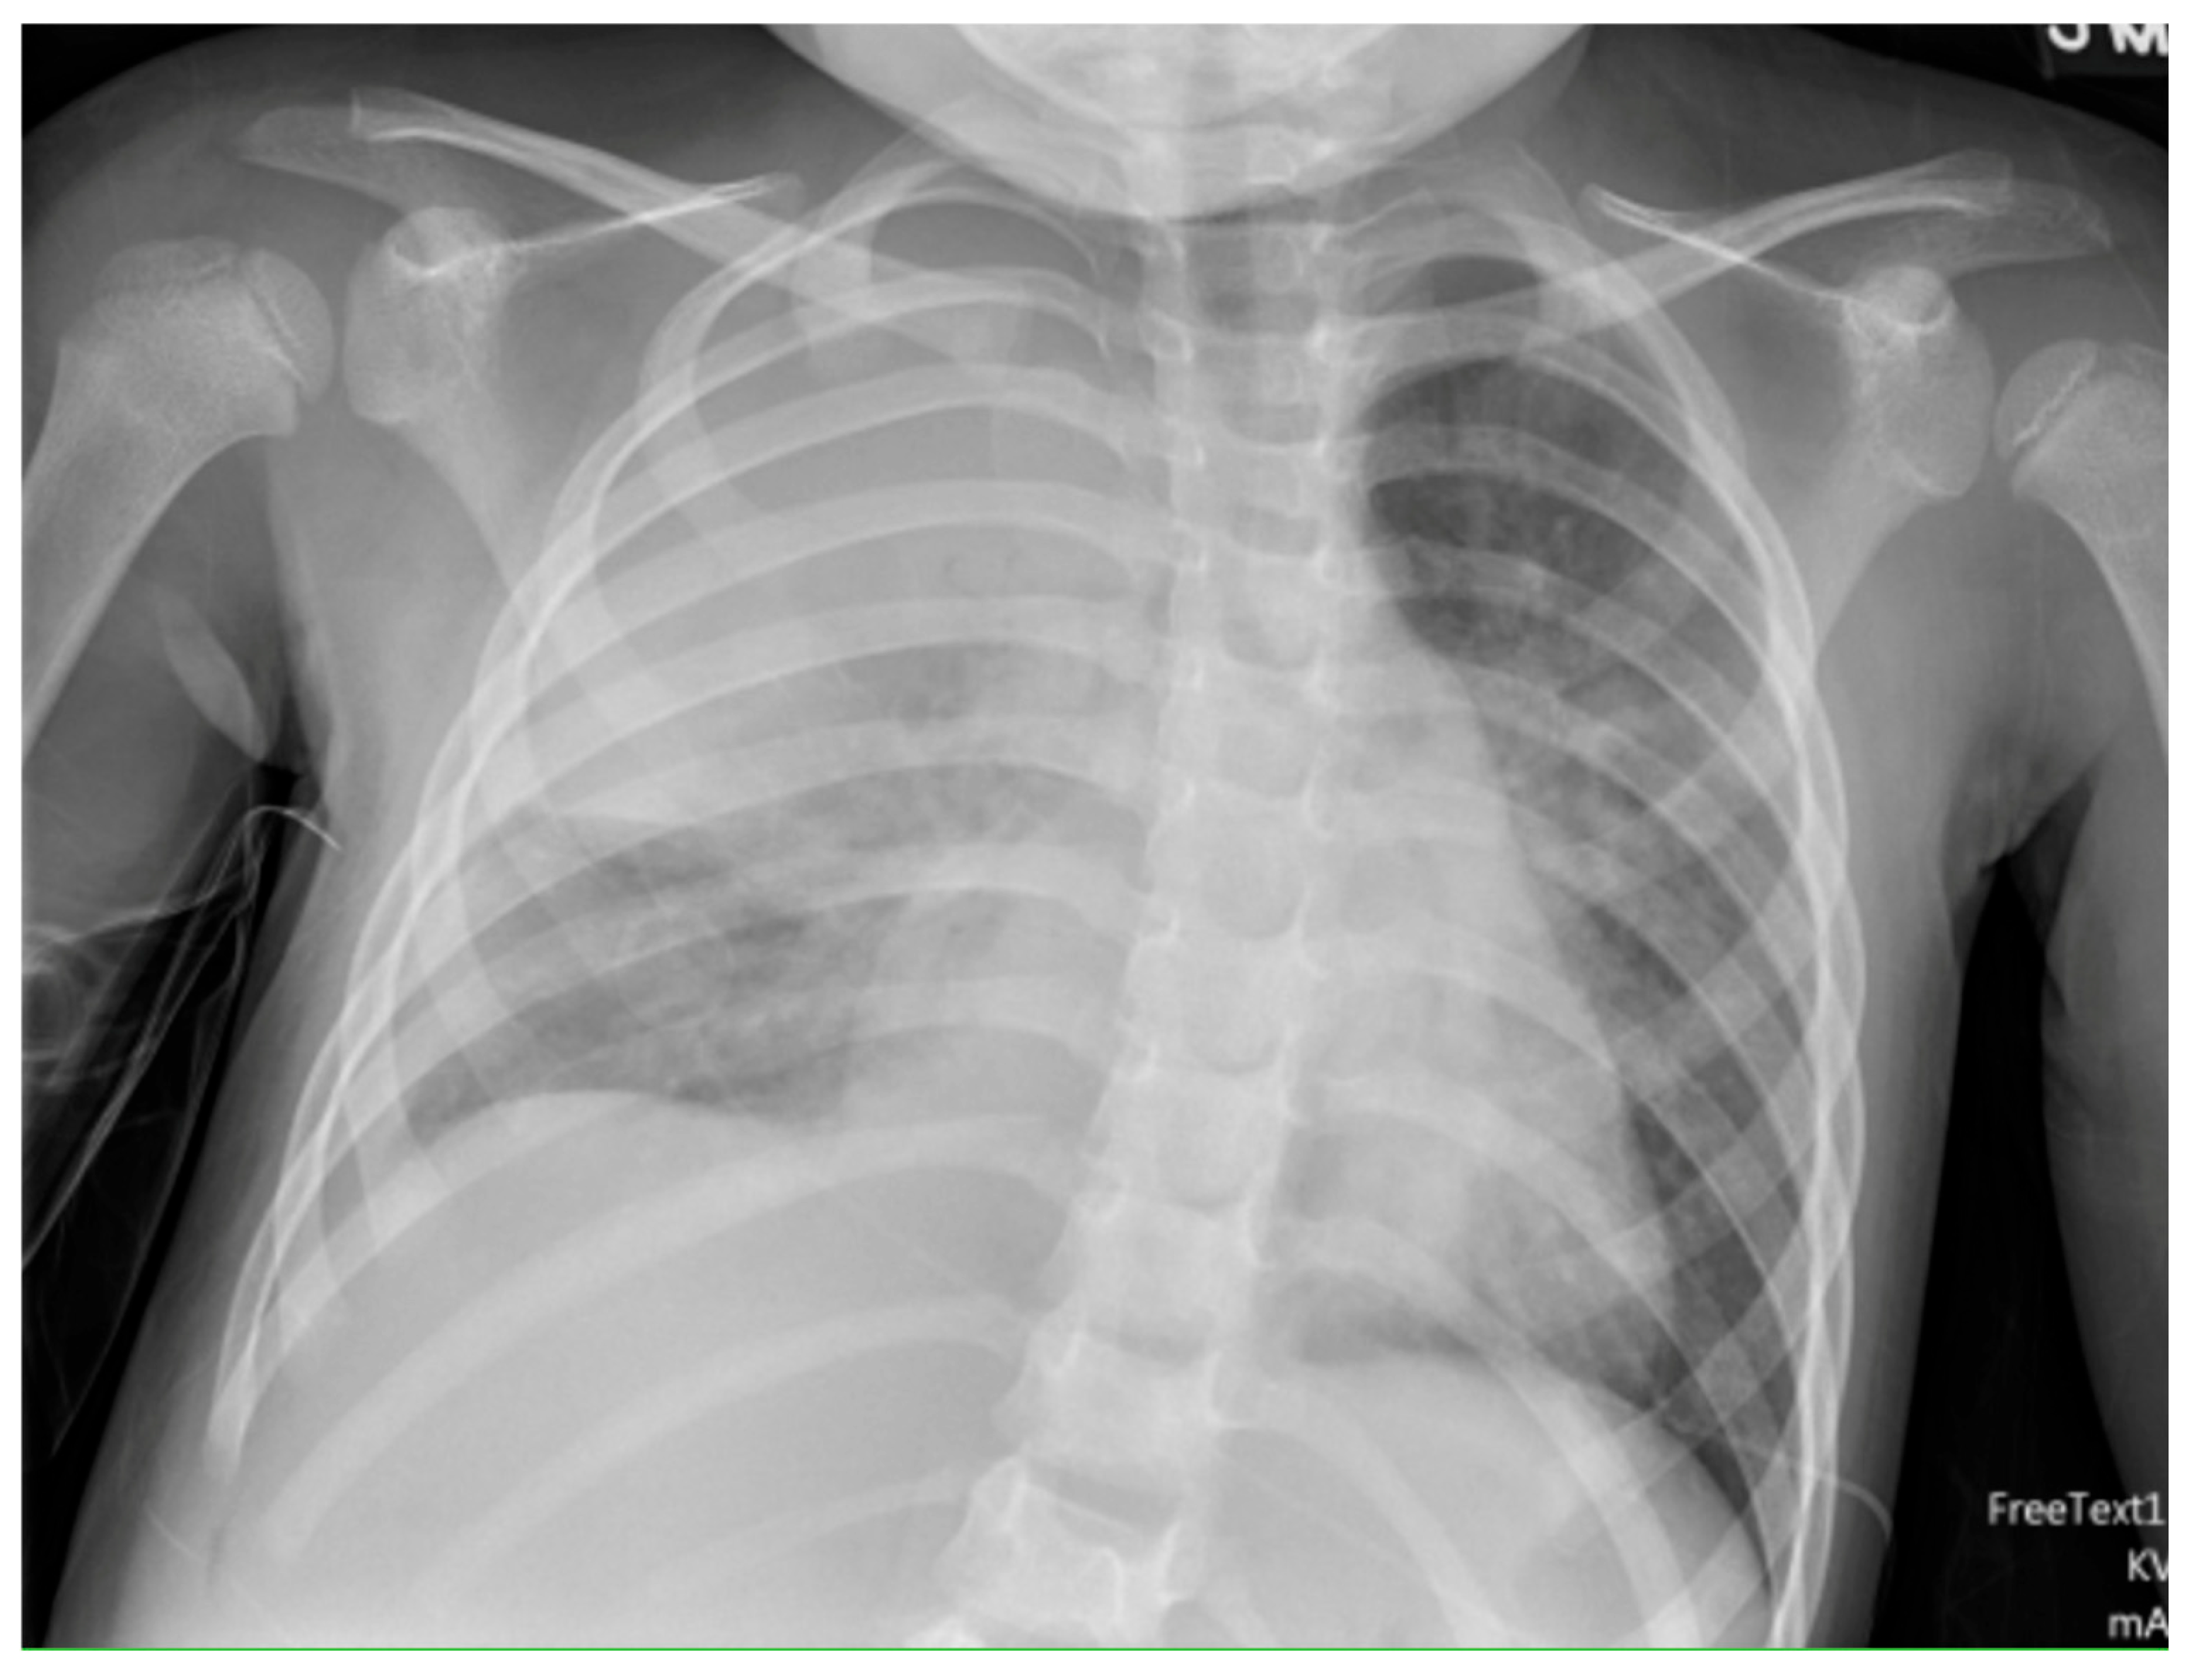

- Huang, W.E.; Matifoll, J.A.; Lord, D.; Haggie, S. A review of imaging in the diagnosis and management of complicated paediatric pneumonia. Paediatr. Respir. Rev. 2025, 54, 12–18. [Google Scholar] [CrossRef]

- Hoffer, F.; Bloom, D.; Colin, A.A.; Fishman, S.J. Lung abscess versus necrotizing pneumonia: Implications for interventional therapy. Pediatr. Radiol. 1999, 29, 87–91. [Google Scholar] [CrossRef]

- Hacimustafaoglu, M.; Celebi, S.; Sarimehmet, H.; Gurpinar, A.; Ercan, I. Necrotizing pneumonia in children. Acta Paediatr. 2004, 93, 1172–1177. [Google Scholar] [CrossRef]

- Tan Kendrick, A.P.; Ling, H.; Subramaniam, R.; Joseph, V.T. The value of early CT in complicated childhood pneumonia. Pediatr. Radiol. 2002, 32, 16–21. [Google Scholar] [CrossRef]

- Hodina, M.; Hanquinet, S.; Cotting, J.; Schnyder, P.; Gudinchet, F. Imaging of cavitary necrosis in complicated childhood pneumonia. Eur. Radiol. 2002, 12, 391–396. [Google Scholar] [CrossRef][Green Version]

- Carrard, J.; Bacher, S.; Rochat-Guignard, I.; Knebel, J.-F.; Alamo, L.; Meuwly, J.-Y.; Tenisch, E. Necrotizing pneumonia in children: Chest computed tomography vs. lung ultrasound. Front. Pediatr. 2022, 10, 898402. [Google Scholar] [CrossRef]

- Kurian, J.; Levin, T.L.; Han, B.K.; Taragin, B.H.; Weinstein, S. Comparison of ultrasound and CT in the evaluation of pneumonia complicated by parapneumonic effusion in children. Am. J. Roentgenol. 2009, 193, 1648–1654. [Google Scholar] [CrossRef] [PubMed]

- Lai, S.-H.; Wong, K.-S.; Liao, S.-L. Value of lung ultrasonography in the diagnosis and outcome prediction of pediatric community-acquired pneumonia with necrotizing change. PLoS ONE 2015, 10, e0130082. [Google Scholar] [CrossRef]